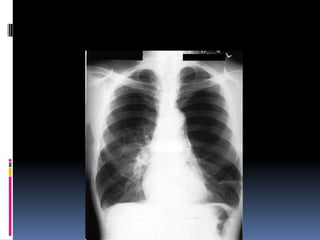

Penetration / Exposure

 Able to see ribs

through the heart

 Barely see the

spine through the

heart

 Pulmonary vessels

can be traced

nearly to the edges

of the lungs

Positioning / Rotation

Does the thoracic spine align in the center of the

sternum and between the clavicles?

Clavicles – equidistant from spine

   Size

   Shape

   Silhouette-margins should be sharp

   Diameter (>1/2 thoracic diameter is

enlarged heart)

 AP views make heart appear larger than it

actually is.

Costo-phrenic / cardiophrenic angles

Margins should

be sharp

Lung fields